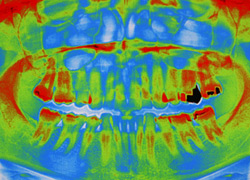

Unsere Praxis ist mit digitalen CCD Röntgensensoren der neuesten Generation ausgestattet. Diese ermöglichen gegenüber der konventionellen zahnärztlichen Röntgentechnik eine Reduktion der Strahlendosis um bis zu 90%. Darüber hinaus sind Auflösung und Kontrastverhalten der Bilder konkurrenzlos. Dies ermöglicht eine extrem schonende und exakte Diagnostik.